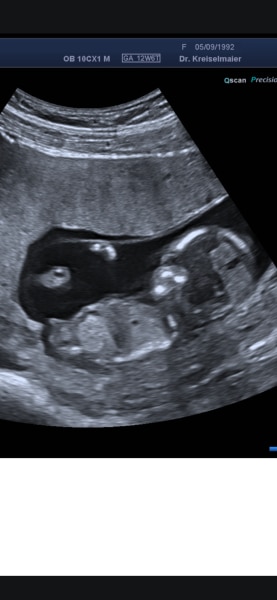

Bild zu Mädchen oder Junge? Erkennt jemand was? - Schwanger - wer noch? Rund um die Schwangerschaft

Der Termin war Anfang letzter Woche er sagt er ist sich eig sicher welches Geschlecht durfte aber noch nichts verraten. Bin jetzt aus der SSW14 raus und dürfte das Geschlecht nun wissen aber wie es nun mal so sein soll hat der Arzt Aufgrund der Ferien eine Woche zu 😅 Erfahre es sicher erste nächste Woche anhand des Bluttest.  Aber ihr könnt gerne Raten dann stell das Ergebnis nächste Woche hier rein :)

Guten Abend Memyselfandi,  verstehe dich voll. Und natürlich sind wie Laien, aber man kann ja nunmal raten und die Wartezeit ein bisschen damit vertreiben 😊  Ich würde tatsächlich auf einen Jungen Tippen. Beim ersten Bild liegt euer Mäuschen recht gerade und der Nub deutet ein wenig nach oben.  Bin auf jedenfall gespannt, wie das Ergebnis sein wird...  Natürlich noch Herzlichen Glückwunsch zur Schwangerschaft und schön, dass sich euer Baby so toll entwickelt 😊